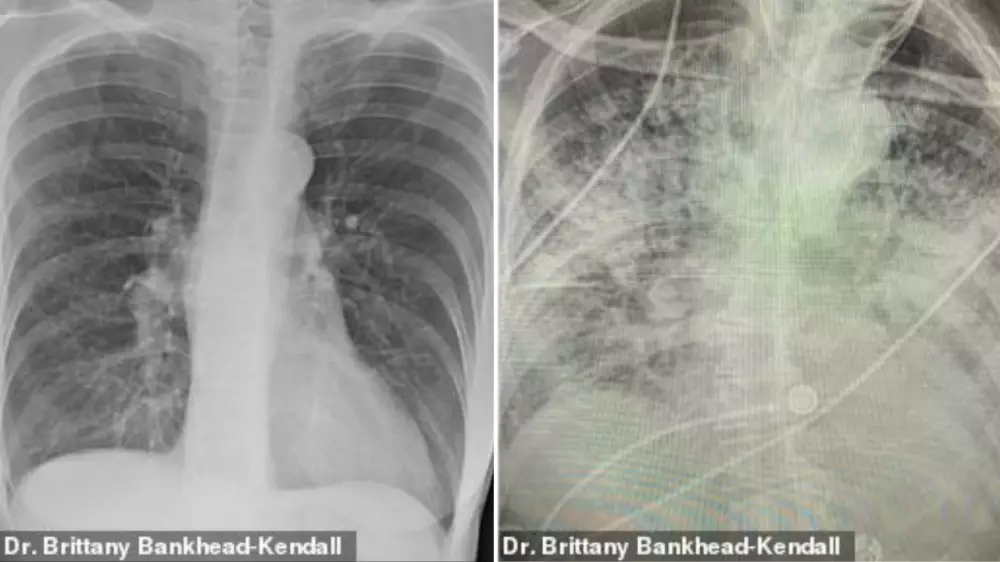

Рентгеновские снимки показали шокирующее состояние легких после заражения COVID-19, передает Tengrinews.kz со ссылкой на Daily Mail.

Доцент Центра медицинских наук Техасского технологического университета, доктор Бриттани Бэнкхед-Кендалл показала три рентгеновских снимка легких: здорового человека, курильщика и пациента с коронавирусом.

По словам хирурга, легкие выздоровевших пациентов с COVID-19 выглядят намного хуже, чем у курильщиков. Снимок выглядел почти полностью белым. Врач пояснила, что помутнение легких обычно указывает на то, что они наполнены такими веществами, как жидкость или бактерии, а также плотными рубцами и повреждениями.

У курильщика они частично побелели от рубцов, и снимок выглядит слегка туманным.

На рентгеновском снимке здорового пациента много черного пространства, что является показателем нормального количества кислорода.

"Легкие после коронавируса выглядят хуже, чем любые ужасные легкие курильщика, которые мы когда-либо видели. И они разрушаются", - заявила она.

По ее словам, многие эксперты в области здравоохранения концентрируют внимание на показателях смертности, а не на долгосрочных последствиях выживших. Доктор Бэнкхед-Кендалл также отметила, что почти у всех пациентов из тех, кого она лечила, и тех, кто переболел коронавирусом, был плохой рентген грудной клетки.